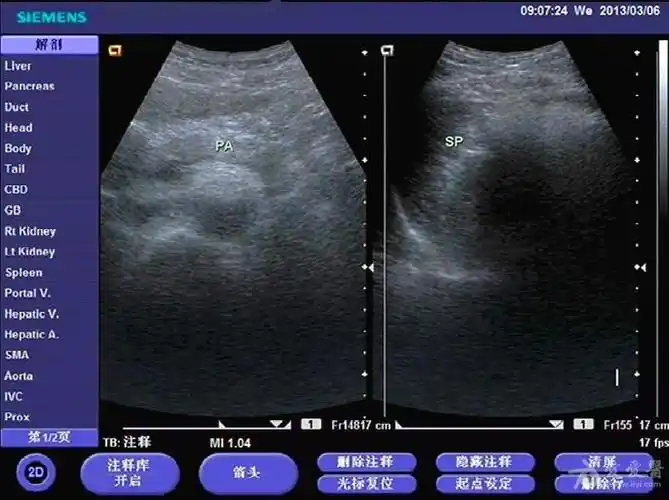

请教脂肪肝门静脉轻度扩张